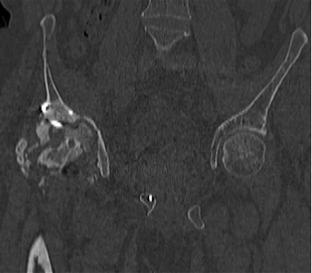

Пациент 49 лет, паровозная травма 23.2.2006, получил вертикальная

нестабильное повреждение таза, разрыв левого крестцово-подвздошного

сочленения, перелом лонной, седалищной костей слева, T-образный

оскольчатый перелом правой вертлужной впадины с переломом заднего

края, вывих правого бедра, посттравматическая пояснично-крестцовая

плексопатия с обеих сторон, паралич мышц правой голени.

В день травмы - вправление вывиха, скелетное вытяжение, 14.3.2006

чрескостный остеосинтез таза. 20.4.2006 остеосинтез правой вертлужной

впадины пластинами, осложнившийся нагноением межмышечной гематомы

правой ягодичной области. Получал консервативное лечение, было

достигнуто полное заживление раны. 24.7.2006 введены илиосакральные

винты слева. С декабря 2006 года и по настоящее время ходит на

костылях без опоры на правую ногу. Планируется THA. Помогите

определиться с вариантом костной пластики? И какую укрепляющую

конструкцию использовать?